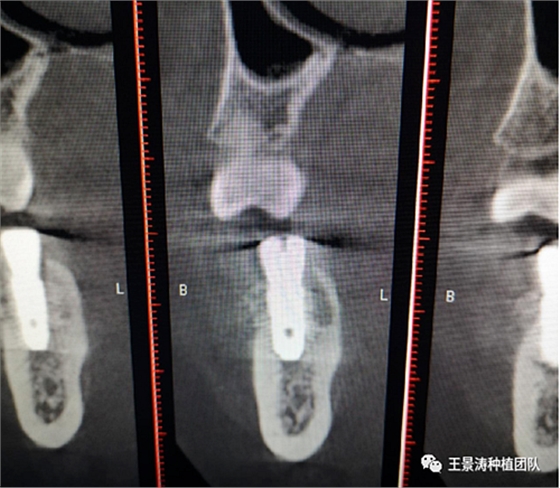

下述病例則是15區(qū)域的即刻種植,15因牙冠折斷于齦下,無法樁核冠修復(fù),則考慮種植修復(fù)。但拍攝CBCT后發(fā)現(xiàn)根尖距上頜竇底距離較短。患者為年輕女性,無全身系統(tǒng)疾病且可利用上頜竇底與根尖皮質(zhì)骨雙側(cè)皮質(zhì)骨固位,且此位置可通過頰側(cè)軟組織減張技術(shù)獲得嚴(yán)密封閉牙槽窩。因其根尖距上頜竇距離較低,遂拔除15后行上頜竇內(nèi)提升,埋入式種植,最終修復(fù)的完成。

患者左側(cè)16慢性根尖周炎,17缺失。16根尖炎癥距上頜竇底較近,需內(nèi)提升,但是因?yàn)閮?nèi)提升后骨質(zhì)較薄所致植入深度過深,埋入式植入。17非埋入式種植。后期效果均可。